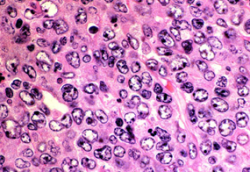

הגדלה מיקרוסקופית של לימפומה של תאי B גדולים, המראה את הפיזור הדיפוזי האופייני של התאים המעניק למחלה את שמה.